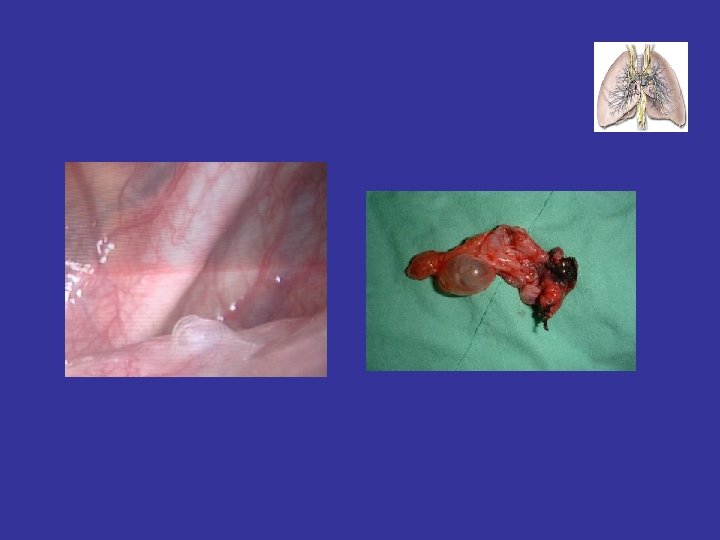

下列何者為自發氣胸之最常見原因: • A. TB • B. Small bleb破裂 • C. Emphysema • D. Lung

下列何者為自發氣胸之最常見原因: • A. TB • B. Small bleb破裂 • C. Emphysema • D. Lung cancer • E. Endometriosis 2021/10/24 10